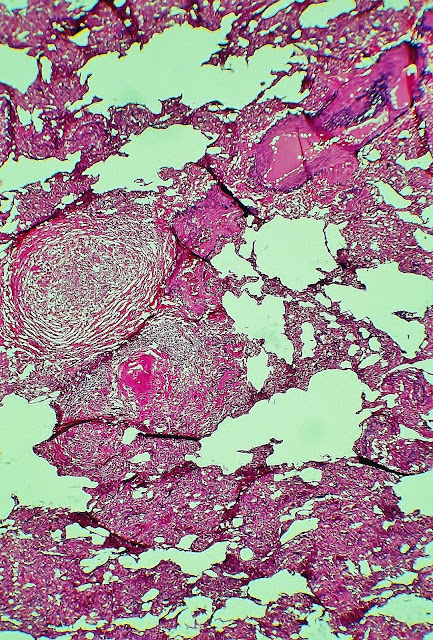

Pulmón.-

Numerosos granulomas, de tamaño variable entre 300-400 micras y varios mm, algunos de los cuales presentan reacción gigantocelular y respuesta linfocitaria.Periféricamente aparecen rodeados por una envoltura formada por gruesas fibras de colágeno, de distribución concéntrica. Los granulomas se encontraban en diferentes estadíos de desarrollo hacia la fibrosis.

The series of photographs shown below were made with techniques silver impregnation (silver methenamine), hematoxylin-eosin-phloxine, staining for elastic fibers and PAS. The photo sequence shown attempts to indicate the different cuts examined to reach the accurate diagnosis of pulmonary hydatid disease. The morphological data target for the diagnosis was the presence of laminated hydatid membrane cuticle layer, or remnants of it, in some of the granulomas shown in recent photographs.

F ig. 1.-Lung. This photo and the following are from serial sections stained with different techniques histology. Sobretinción PAS technique and with elastic. The picture shows the amorphous, PAS positive located in the center of both granulomas. The top granuloma located in the vicinity of a bronchiole. Prof.Garfia.A

Fig.1.A-Lung. In the center of both granulomas distinguishes amorphous PAS positive material. Prof.Garfia.A